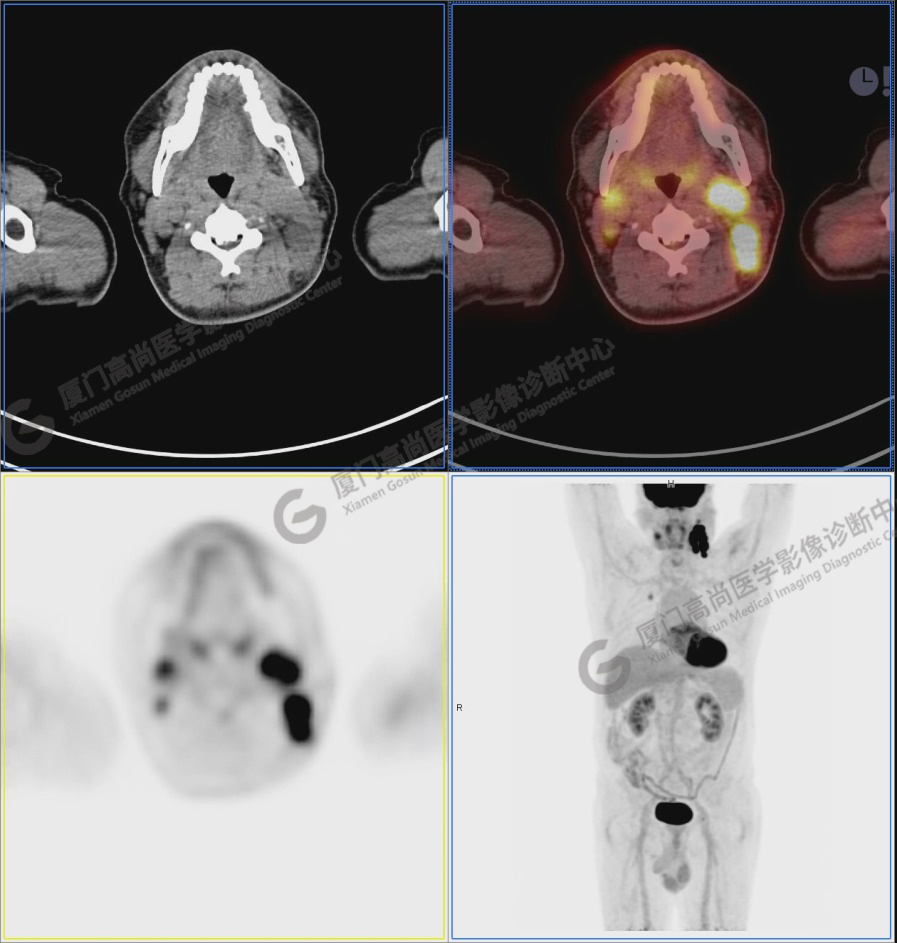

Z先生,58歲,發(fā)現(xiàn)左頸部淋巴結(jié)腫大半年余。淋巴結(jié)穿刺活檢示:增生纖維組織中少量異型梭形細胞,伴炎癥細胞浸潤,考慮惡性腫瘤。既往史:高血壓數(shù)年,否認糖尿病、肝炎、結(jié)核、甲亢。無吸煙嗜好,少量飲酒30年余。無家族腫瘤史。

圖1:PET/CT全身圖像

圖2:雙側(cè)頸部多發(fā)增大淋巴結(jié),代謝不同程度增高,考慮為轉(zhuǎn)移。